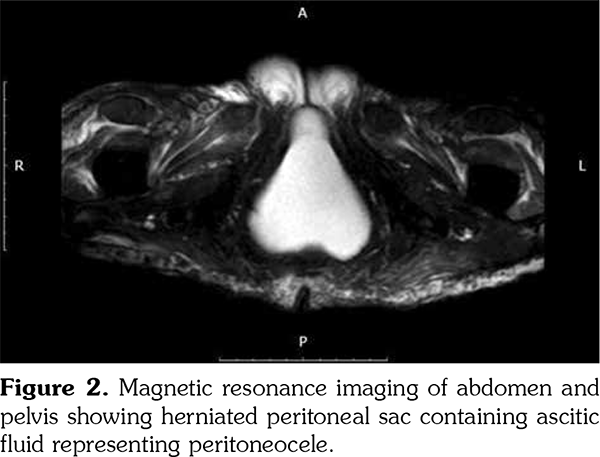

We performed extended investigations that showed normal blood albumin level. Tumor markers were significant only for an elevated serum cancer antigen 125 (CA-125) (80 U/L normal <35). Work-up for TB was negative including adenosine deaminase and polymerase chain reaction in ascitic sampling. Cytology was negative for malignant cells. We conducted computed tomography scan for the chest, abdomen and pelvis with contrast showing massive ascites with ill-defined omental thickening related to the anterior abdominal wall. A cystic lesion was seen at perineal region, minimal bilateral pleural effusion and massive abdominal ascites. Laparotomy and biopsy were performed revealing fat necrosis. Subsequently, magnetic resonance imaging of the abdomen and pelvis was conducted but it was insignificant apart from massive ascites with adhesions. No ovarian masses were observed (Figure 1). In lower perineal region, herniating peritoneal sac was noted containing ascitic fluid representing peritoneocele (Figure 2).